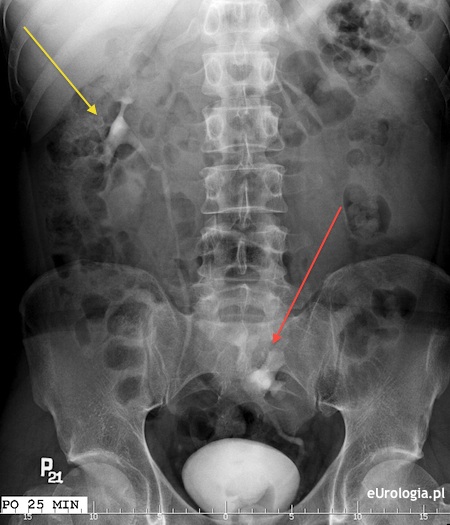

Fot. Ektopia miednicza lewej nerki - obraz urograficzny.